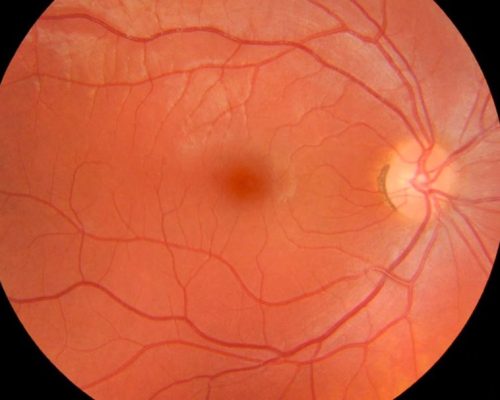

Mapeamento de Retina: um cuidado essencial para a saúde dos seus olhos

Outubro 19, 2025

O mapeamento de retina é um exame fundamental para avaliar a saúde ocular de forma